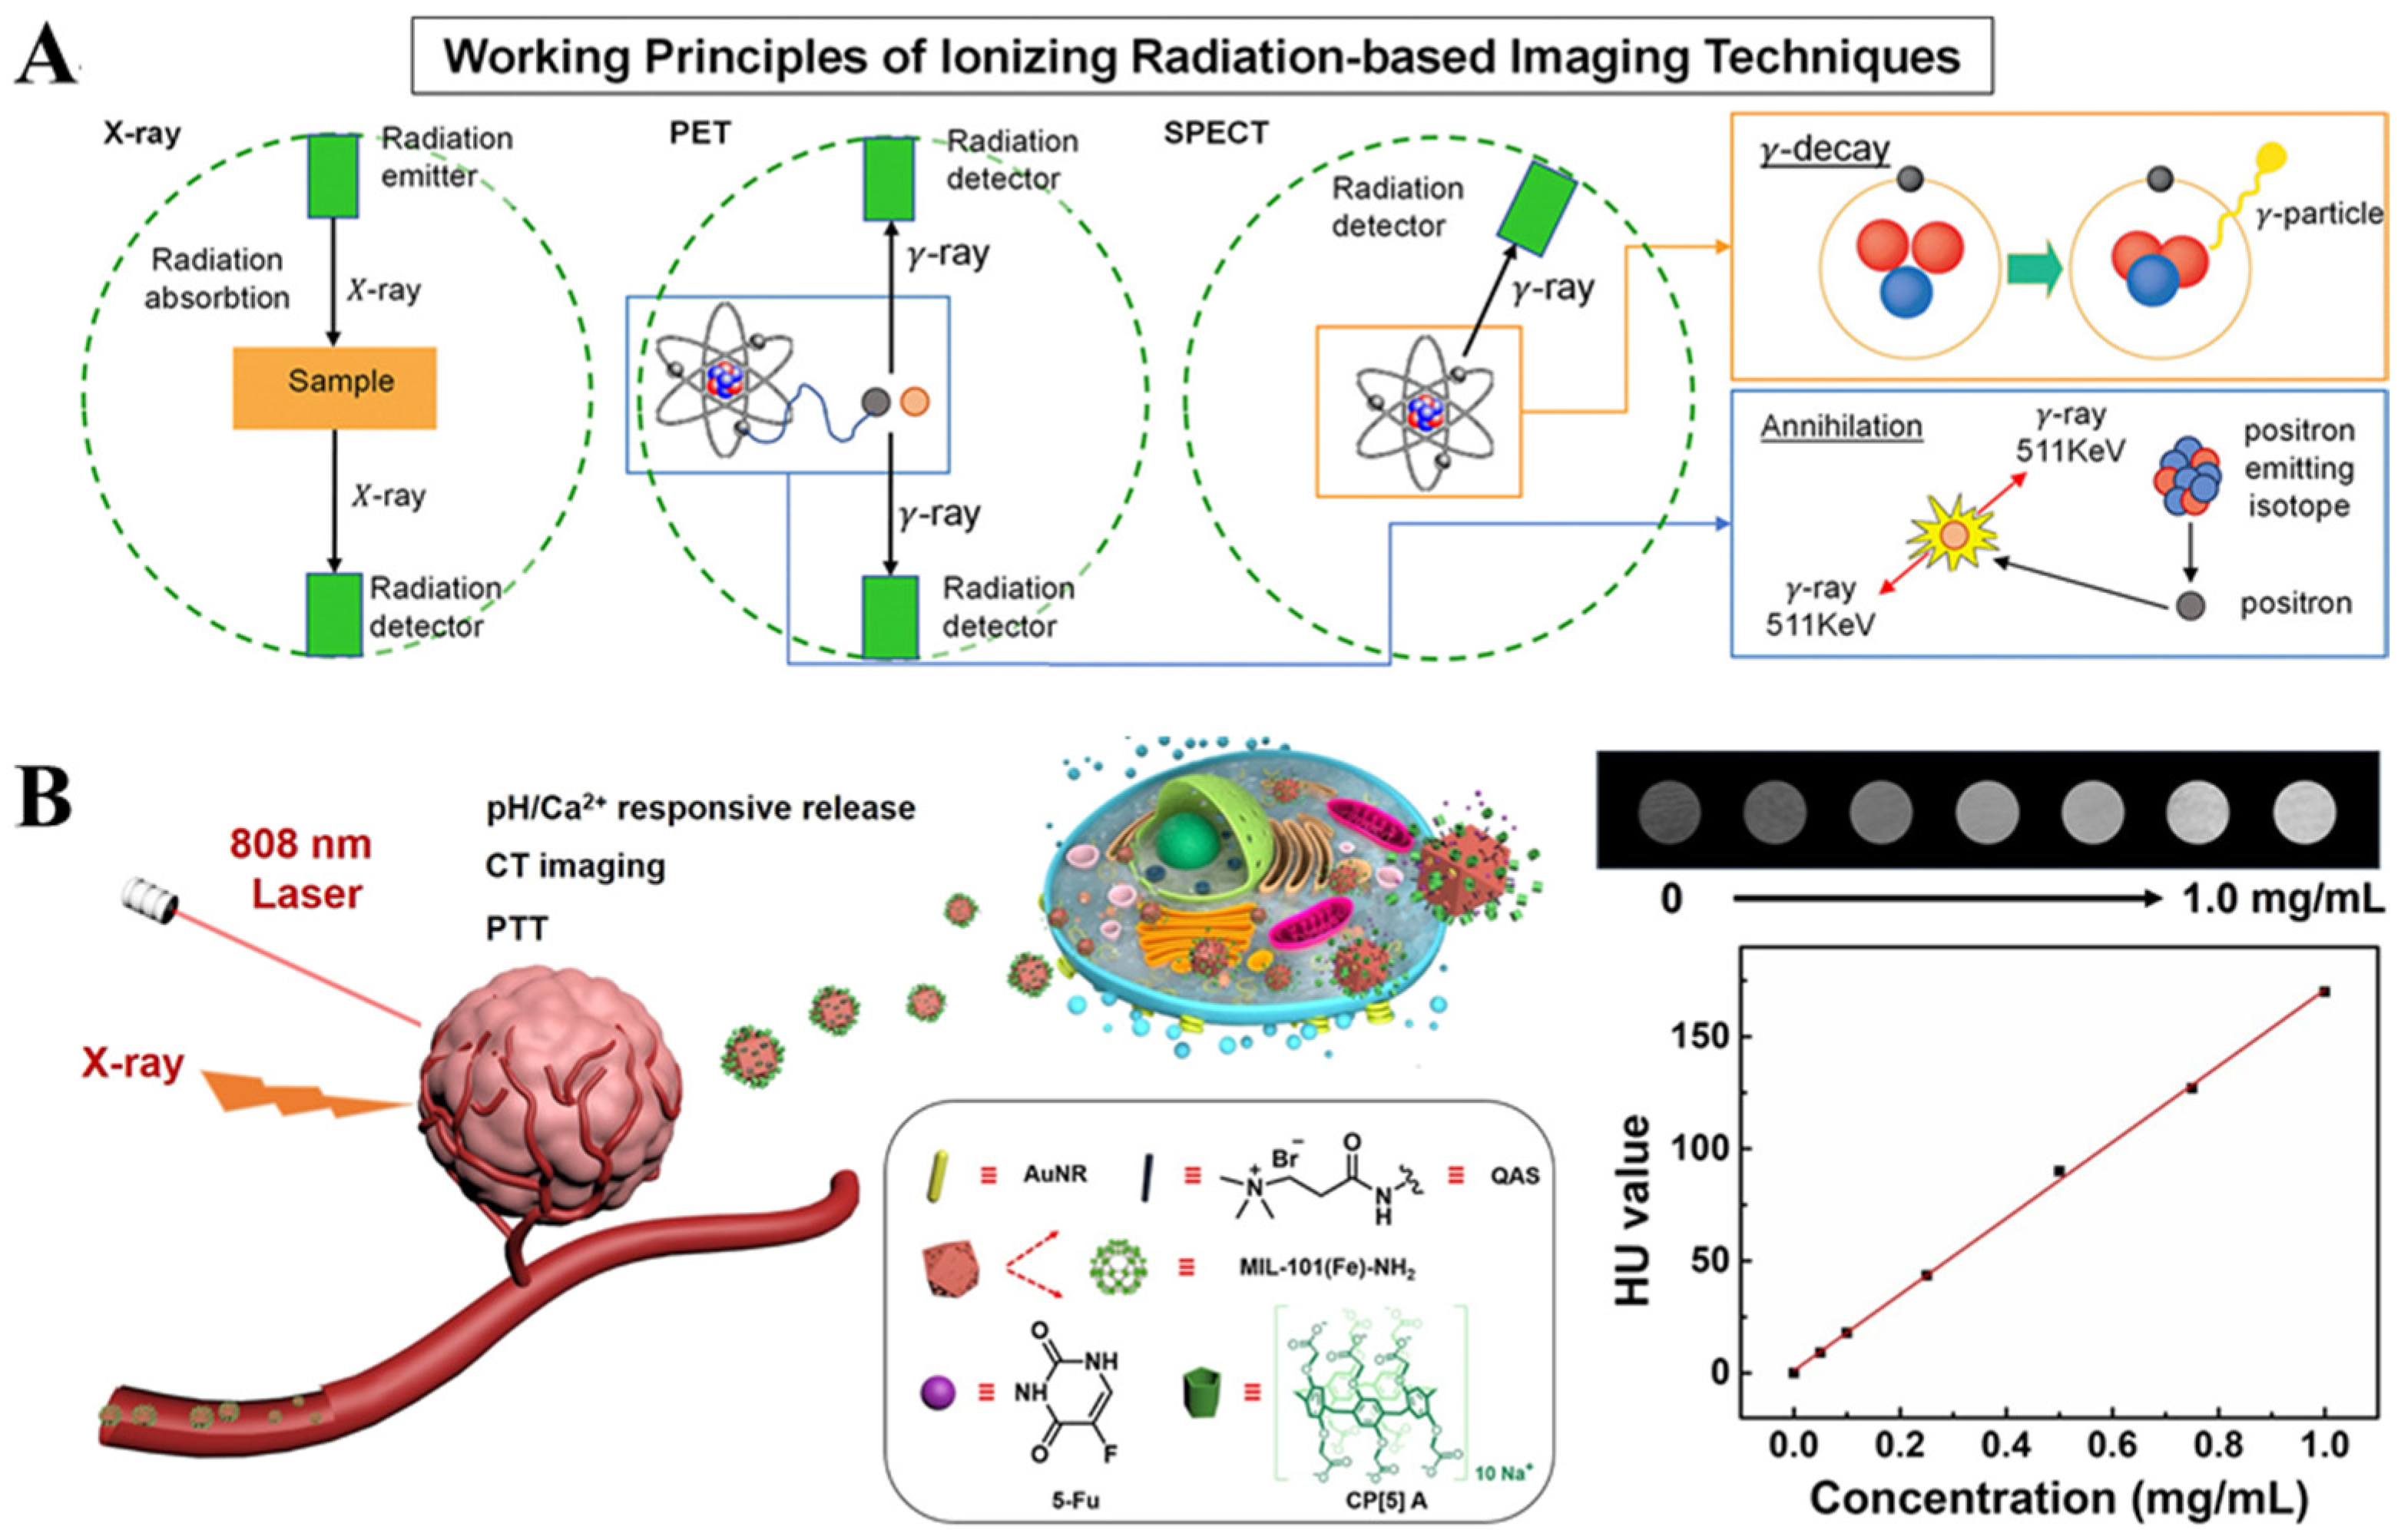

2.4. Ionizing Radiation-Based Techniques

- Gao, J.; Yu, H.M.; Wu, M.; Chen, Q.; Yang, Y.; Qu, Y.; Sun, M.; Qin, J.C.; Ma, L.; Yang, Y.W. AuNRs@MIL-101-based stimuli-responsive nanoplatform with supramolecular gates for image-guided chemo-photothermal therapy. Mater. Today Chem. 2022, 23, 100716. [Google Scholar] [CrossRef]